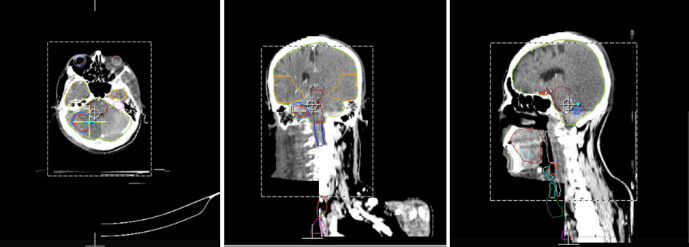

放疗过程中,患者的治疗前正确摆位是精准放疗的前提条件,传统的CT模拟复位和治疗床值复位不仅效率低且无法精确评估。图像引导技术可通过机载的锥形束CT扫描仪对患者进行在线扫描,可进行摆位误差修正和实时诊断。除此之外,肺部和腹部肿瘤在治疗过程中随着呼吸运动会有一定的运动范围,使用特定的4D-CBCT扫描方式可对患者的靶区进行实时追踪,从而实现精准照射。